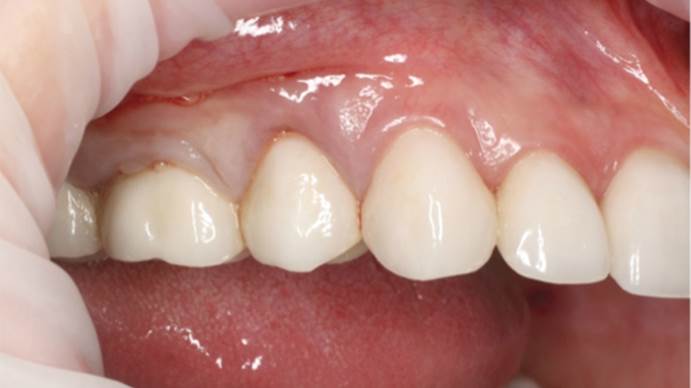

Clinical case: AnyRidge immediate loading

- Courtesy of Dr. Andres Paraud Freixas, Chile -

Keywords

AnyRidge, ISQ value, initial stability, immediate loading, KnifeThread, maxillary anterior, Mega ISQ, Dr. Andres Paraud Freixas

“Patient’s smile was recovered on the day of surgery

with reliable & highly-aesthetic results using AnyRidge & R2GATE. ”